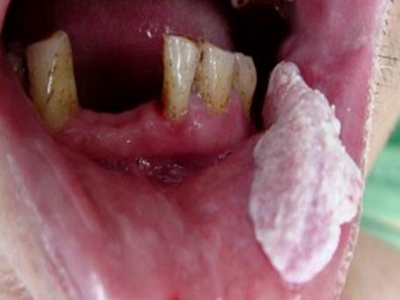

唇内侧

白斑

口腔毛状黏膜白斑下嘴唇内侧白斑图

口腔毛状黏膜白斑的患者在嘴唇内侧出现白色斑块,表现为大片分布的块状白斑,表面粗糙有颗粒感,有条状纹路,患者自觉有轻微疼痛感。